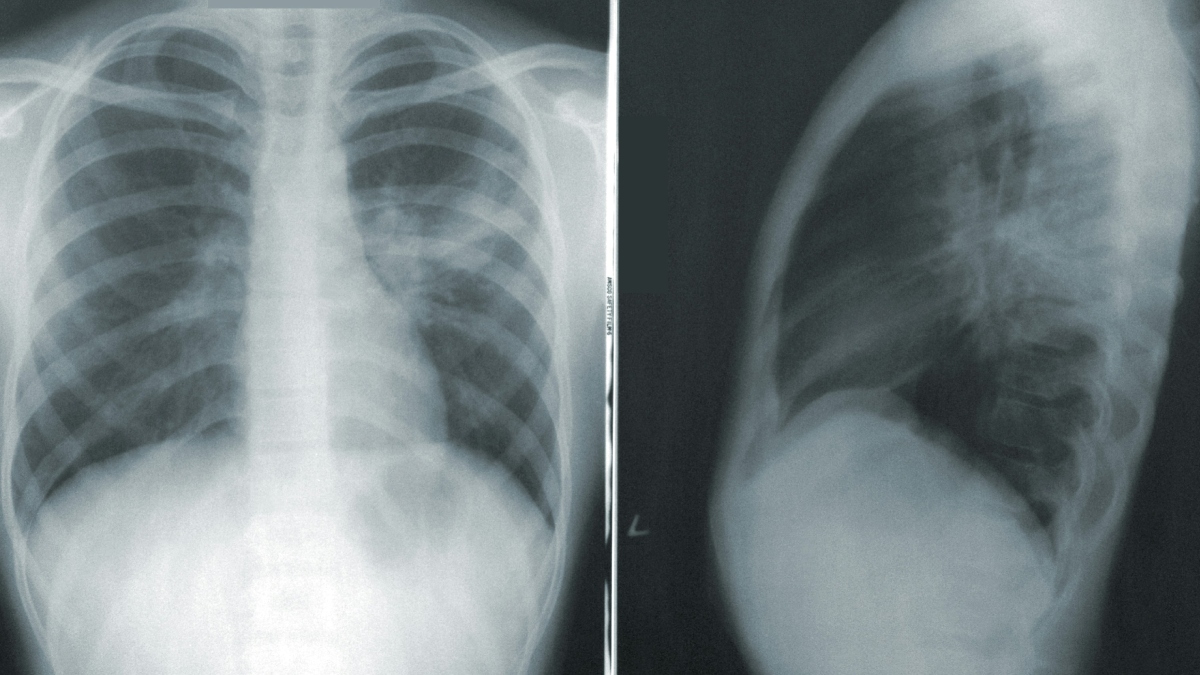

Καρκίνος του πνεύμονα: Μπορεί να εμφανιστεί και σε ανθρώπους που δεν κάπνισαν ποτέ στη ζωή τους

Και πράγματι, για δεκαετίες η σύνδεση αυτή ήταν τόσο ισχυρή, ώστε σχεδόν επισκίασε μια άλλη σημαντική πραγματικότητα: ο καρκίνος του πνεύμονα μπορεί να εμφανιστεί και σε ανθρώπους που δεν κάπνισαν ποτέ στη ζωή τους. Αυτή η μορφή της νόσου αναγνωρίζεται πλέον όλο και περισσότερο ως μια ξεχωριστή βιολογική και κλινική οντότητα, με δικά της χαρακτηριστικά, διαφορετικούς μηχανισμούς εμφάνισης και ιδιαίτερες προκλήσεις στη διάγνωση και την αντιμετώπιση.

Σήμερα ο καρκίνος του πνεύμονα εξακολουθεί να αποτελεί μία από τις κυριότερες αιτίες θανάτου από καρκίνο παγκοσμίως. Ωστόσο, ενώ τα ποσοστά ενεργού καπνίσματος μειώνονται σε πολλές χώρες, οι περιπτώσεις καρκίνου του πνεύμονα σε μη καπνιστές φαίνεται να αποκτούν ολοένα μεγαλύτερη σημασία. Υπολογίζεται ότι ένα αξιοσημείωτο ποσοστό των περιστατικών αφορά ανθρώπους που δεν κάπνισαν ποτέ ή κάπνισαν ελάχιστα στη ζωή τους.

Αυτό που κάνει αυτή τη νόσο τόσο ύπουλη είναι ότι οι ασθενείς αυτοί δεν ταιριάζουν στο «κλασικό» προφίλ κινδύνου. Δεν έχουν το ιστορικό καπνίσματος που θα κινητοποιούσε άμεσα γιατρούς και συστήματα υγείας να τους παρακολουθήσουν στενά. Έτσι, πολλές περιπτώσεις διαγιγνώσκονται σε προχωρημένο στάδιο, όταν τα συμπτώματα έχουν ήδη εμφανιστεί και η νόσος είναι πιο δύσκολο να αντιμετωπιστεί. Με άλλα λόγια, ένα σημαντικό κομμάτι του πληθυσμού παραμένει εκτός του παραδοσιακού ραντάρ πρόληψης και έγκαιρης διάγνωσης.